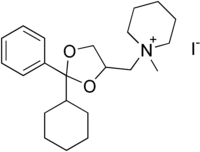

| IUPAC name

1-[(2-cyclohexyl-2-phenyl-1,3-dioxolan-4-yl)methyl]-1-methylpiperidin-1-ium iodide | |

| C22H34INO2 | |

| Molar mass | 471.42 g/mol |

Oxapium iodide (ciclonium or cyclonium, trade name Oxaperan) is an antispasmodic indicated for the treatment of gastritis, gastroduodenal ulcer, enteritis, and other conditions. It is marketed in South Korea by Dongsung Pharmaceuticals.